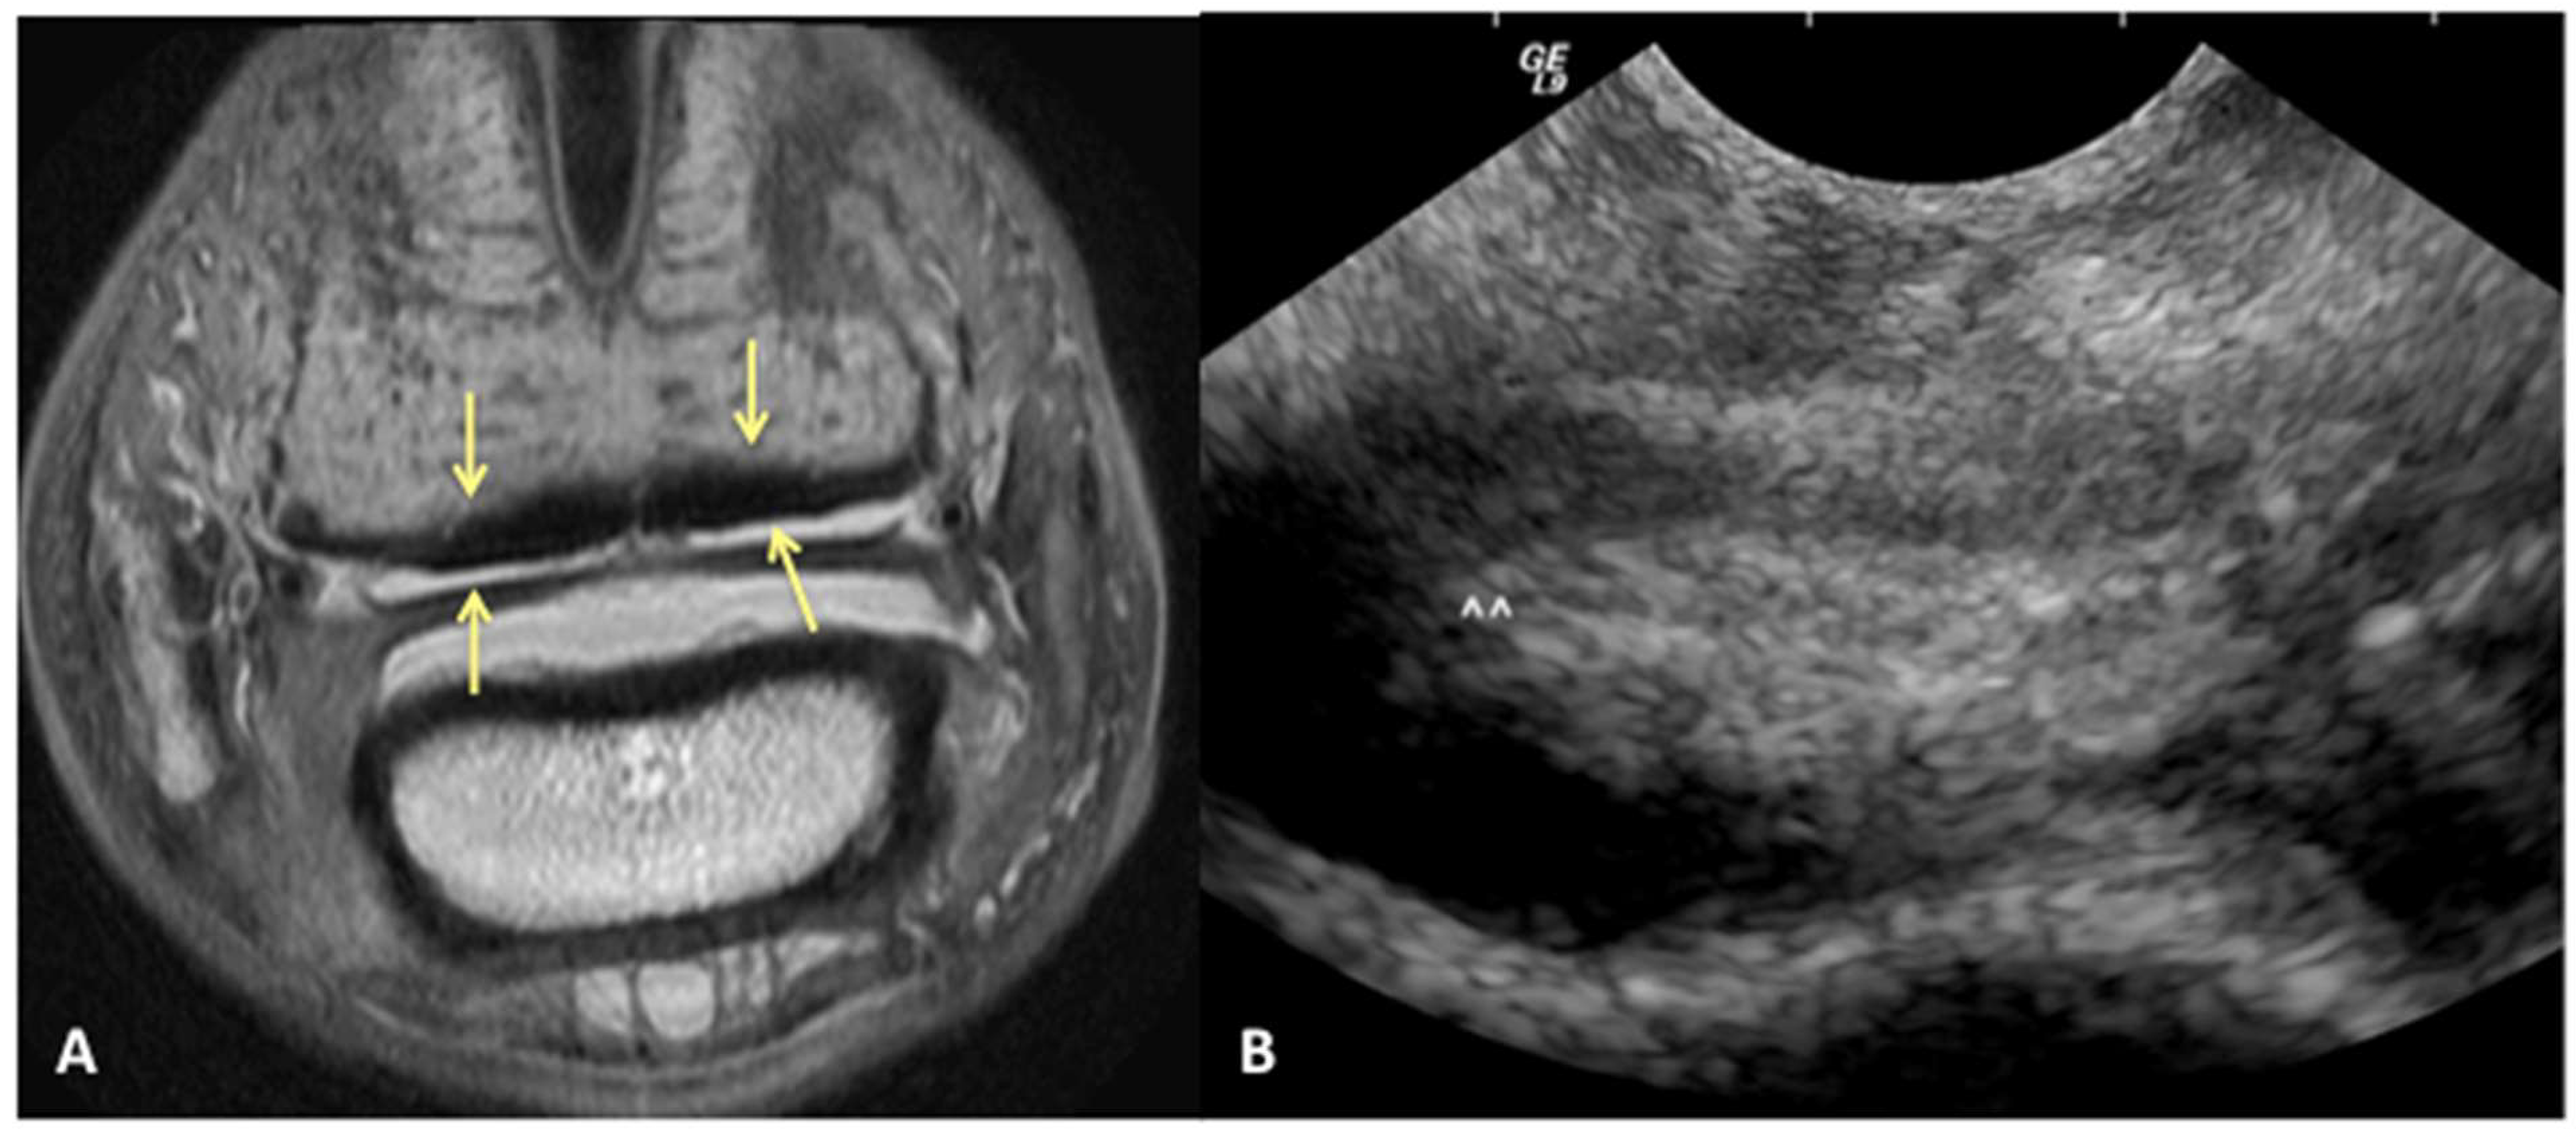

We can reject the other part of our hypothesis that ultrasound will under-diagnose the amount of injury to the DDFT. While ultrasound was good for evaluating the dorsal surface tearing of the DDFT at the level of the navicular bursa, with a sensitivity of 85%, it had a lower specificity of 60%. This lower specificity indicates that we could have less ability to truly rule in a lesion of the DDFT as diagnosed by ultrasound. Of the 43/70 limbs that did not have evidence of DDFT dorsal surface tearing on MRI, 17 were over-diagnosed as having tearing or bulging of the dorsal surface on ultrasound (Figure 4). This was a surprising finding, in part because the authors tend to be conservative in their assessment of the DDFT in this location. However, imaging the navicular bursa and DDFT within the hoof capsule is limited by probe position and angle of incidence. On and off-angle imaging cannot be used to help distinguish the borders of objects located distally within the hoof capsule, and drop-out artifacts can artifactually enhance the appearance of DDFT lobe enlargement. Additionally, although the researchers are trained to be as objective as possible, there is likely some degree of unconscious bias towards suspecting abnormalities when performing an ultrasound on a horse diagnosed with pain originating from the digit.

Figure 4. Transverse proton dense MR image (A) and corresponding ultrasound image (B) at the level of the collateral sesamoidean ligament and proximal recess of the navicular bone. Dorsal bulging and tearing was identified on ultrasound in the lateral lobe, white arrow heads; however, the DDFT is normal on MRI (yellow arrows). Palmar is on the top of the image, dorsal is on the bottom of the image, lateral is on the left.